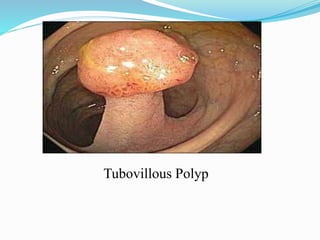

This document discusses colorectal polyps. It defines polyps and describes their types, including neoplastic and non-neoplastic polyps. It discusses adenomatous polyps in depth, noting their malignant potential increases with size over 1cm and villous architecture. Radiological diagnostic methods for polyps including single and double contrast barium enema and CT colonography are explained. The document provides an overview of polyp pathogenesis and genetic syndromes like FAP that increase cancer risk.